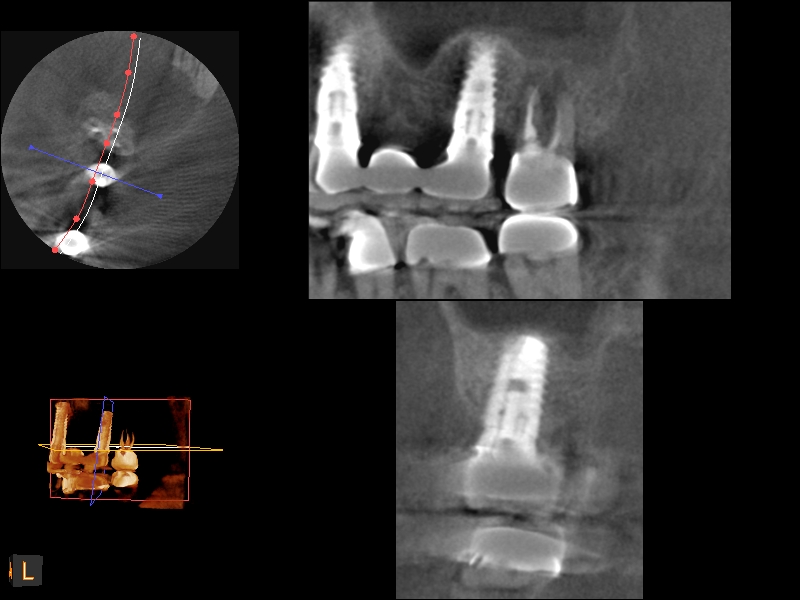

A 4-month CBCT scan (Kodak 9000D) of

implant No. 14.

Fig. 7

CBCT scan (Kodak 9000D) of implant No. 14 showing homogeneous appearance of the bone.

Fig. 19